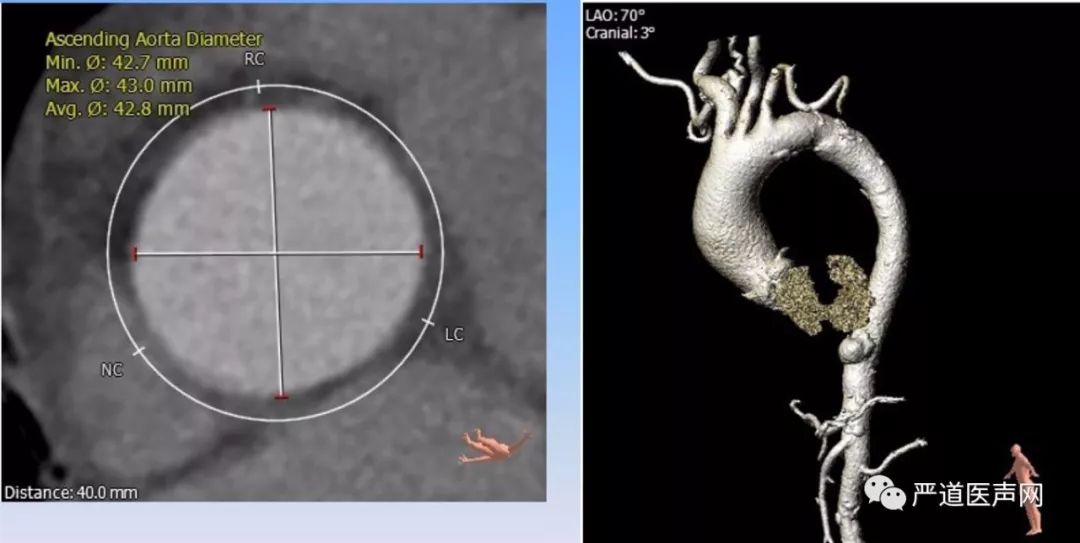

TAVR CTA分析结果

主动脉瓣瓣环直径 29.7*23.7 mm,瓣环周长84.6mm,面积557.5mm2,主动脉窦部直径32.1mm*30.6mm*35.2mm,左心室流出道周长89.6mm,面积584.5mm2。(如下图)

CTA提示患者瓣膜重度钙化,Type I型二叶主动脉瓣,横位心,主动脉与左心室夹角67°。(如下图)

升主动脉42.8mm,降主动脉可见明显主动脉穿透性溃疡(如下图)。外周血管入路条件良好。

升主动脉42.8mm,降主动脉可见明显主动脉穿透性溃疡(如下图)。外周血管入路条件良好。